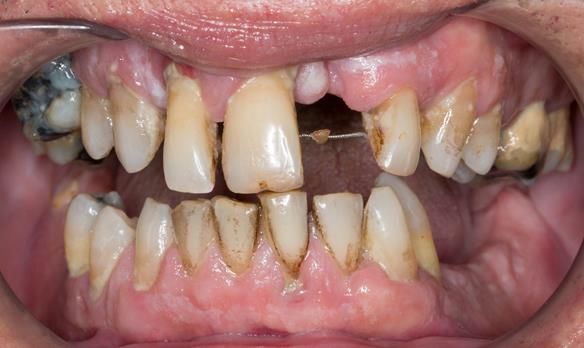

This 52 year old man was referred to me from his general dental practitioner in 2018.

10 years prior to consultation the patient's general dentist diagnosed periodontitis and referred him to Manchester Dental Hospital. He received a treatment plan to manage the periodontitis. Unfortunately, this was not acted on. Four years ago gaps developed between the upper front teeth. Orthodontic treatment was provided to align the teeth. A bonded retainer was fitted onto the upper front teeth. Approximately one year prior to consultation with me the patient noticed the teeth moving again. He consulted his orthodontist, who advised no further orthodontic treatment. One month prior to the consultation with me the upper left central incisor fell out whilst eating.

- Generalised periodontitis; stage IV grade C: currently unstable, risk factors: smoker.

- The remaining maxillary teeth had hopeless prognosis in the short term. They exhibited 80 - 100% alveolar bone loss with increased mobility (Grade 2 - 3).

- The lower right second premolar and lower left first premolar (LR5 LL4) had hopeless prognosis in the short term. They exhibited 80 - 100% alveolar bone loss with grade 3 mobility.

- The remaining mandibular teeth had approximately 30 - 50% alveolar bone loss with grade 1 mobility.